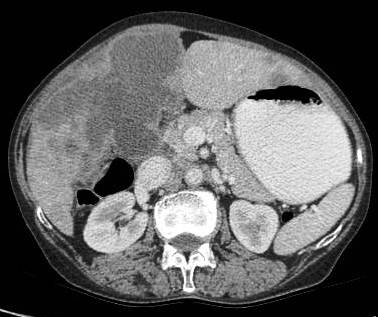

Common patterns of carcinoma gallbladder

Three patterns have been described on ultrasonography (US). The gallbladder fossa is replaced by a heterogeneous mass (figure 1) with internal areas of necrosis; or there may be diffuse, irregular, and asymmetrical wall thickening (Figure 2); or less commonly, a polypoidal, fungating intra-luminal mass is seen. Correct preoperative diagnosis has improved considerably with the use of newer imaging techniques [6-8]. Majority of cases when diagnosed, are no longer resectable (Figure 3) [9-11].

Figure 2: diffuse infiltrative carcinoma of the gallbladder with irregular wall thickening and invasion of liver parenchyma. Medially the plane with second part of duodenum is invaded. Inferiorly right perinephric fat plane invaded